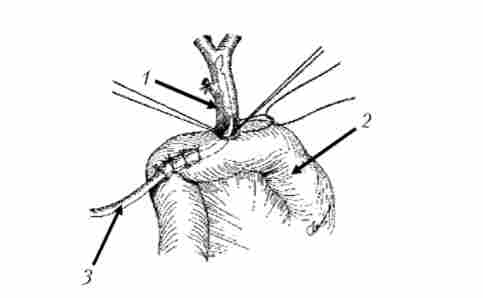

Схема операції накладення обхідного гепатікоеюноанастомоз при раку головки підшлункової залози, ускладненому механічною жовтяницею

Мал. 21.15. Схема операції накладення обхідного гепатікоеюноанастомоз при раку головки підшлункової залози, ускладненому механічною жовтяницею. Анастомоз сформований на дренажі, виведеному через анастомозірованной кишку: